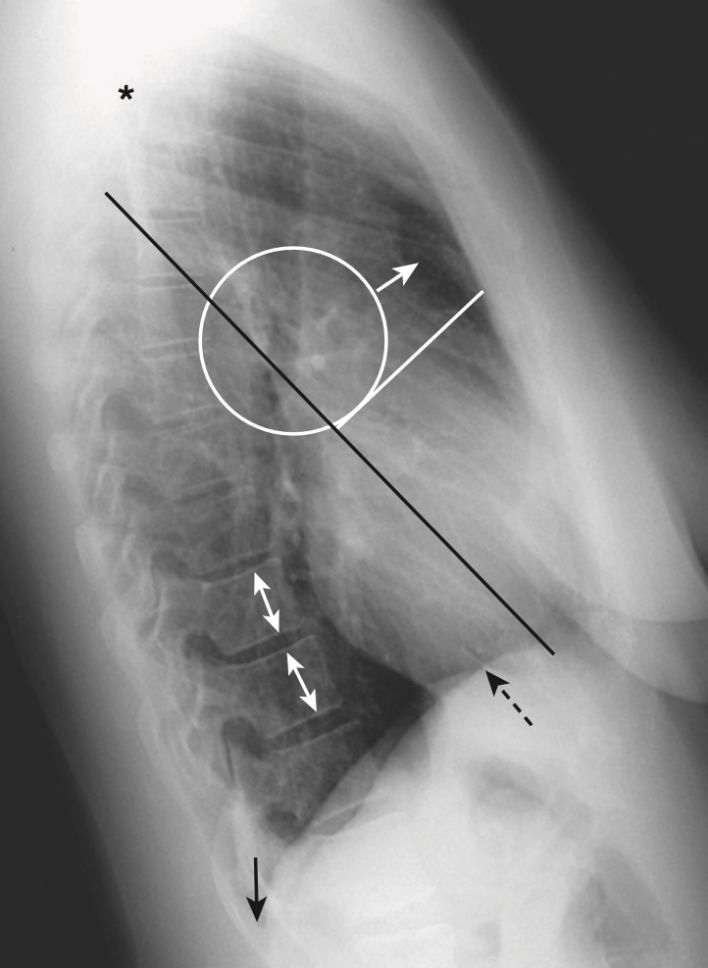

- Hình 3 hiển thị một số đặc điểm giải phẫu bình thường có thể nhìn thấy trên phim X quang ngực nghiêng.

Năm vùng chính trên phim chụp X-quang ngực nghiêng (bên)

(xem Hình 3 và Bảng 3-1)

- Khoảng trống sau màng xương ức

- Vùng rốn phổi

- Các rãnh

- Cột sống ngực

- Cơ hoành và góc sườn hoành sau.

- Trên phim nghiêng, có thể nhìn thấy cả rãnh lớn (chéo) và bé (ngang) dưới dạng các đường nhỏ, màu trắng (dày khoảng bằng đường kẻ bằng đầu bút chì). Các rãnh phân định các thùy trên và dưới ở bên trái và các thùy trên, giữa và dưới ở bên phải.

- Các rãnh lớn chạy theo hướng chéo, khoảng từ mức của đốt sống ngực thứ 5 đến một điểm trên bề mặt cơ hoành của màng phổi sau xương ức vài cm. Rãnh bé nằm ngang mức xương sườn thứ 4 trước (chỉ có ở bên phải) và hướng theo chiều ngang (xem Hình 3).

Cơ hoành (diaphragm) và ngách sườn hoành sau (posterior costophrenic sulci)

- Nửa cơ hoành phải thường có thể nhìn thấy được toàn bộ chiều dài của nó từ trước ra sau. Bình thường, nửa cơ hoành bên phải hơi cao hơn bên trái, trên phim chụp X quang nghiêng cũng như thẳng.

- Nửa cơ hoành trái được nhìn rõ ở phía sau nhưng bị bóng bởi cơ tim ở phía trước (tức là mép của nó biến mất ở phía trước) (Hình 10).

- Không khí trong dạ dày hoặc đại tràng góc lách nhìn thấy ngay dưới nửa cơ hoành trái. Gan nằm bên dưới nửa cơ hoành phải, và thường không thấy hơi ruột giữa gan và nửa cơ hoành phải.

Các góc sườn hoành sau (posterior costophrenic sulci)

- Mỗi nửa cơ hoành tạo ra một vòm tròn lõm vào phần trung tâm của đáy mỗi phổi giống như đáy của một chai rượu vang. Điều này tạo ra một chỗ hạ thấp, hay còn gọi là sulcus (ngách), bao quanh ngoại vi của mỗi phổi và là điểm thấp nhất của khoang màng phổi khi người bệnh ở tư thế dựng thẳng.

- Trên phim chụp X quang ngực thẳng, các ngách này dễ dàng nhìn thấy nhất ở rìa ngoài của phổi gọi là ngách sườn hoành bên (còn được gọi là góc sườn hoành bên) và trên phim chụp X quang nghiêng là ngách sườn hoành sau (còn được gọi là góc sườn hoành sau) (xem Hình 1 và 3).

- Thông thường, tất cả các ngách sườn hoành đều có đường viền sắc nét và góc nhọn.

- Tràn dịch màng phổi tích tụ trong các hốc sâu của ngách sườn hoành khi bệnh nhân ở tư thế dựng thẳng, sẽ lấp đầy các góc nhọn này, gọi là tù góc sườn hoành.

- Chỉ cần khoảng 75 mL dịch (hoặc ít hơn) để làm tù góc sườn hoành trên phim nghiêng, trong khi cần khoảng 250 đến 300 mL dịch để làm tù góc sườn hoành trên phim thẳng (xem Hình 10 và Bảng 3-1).